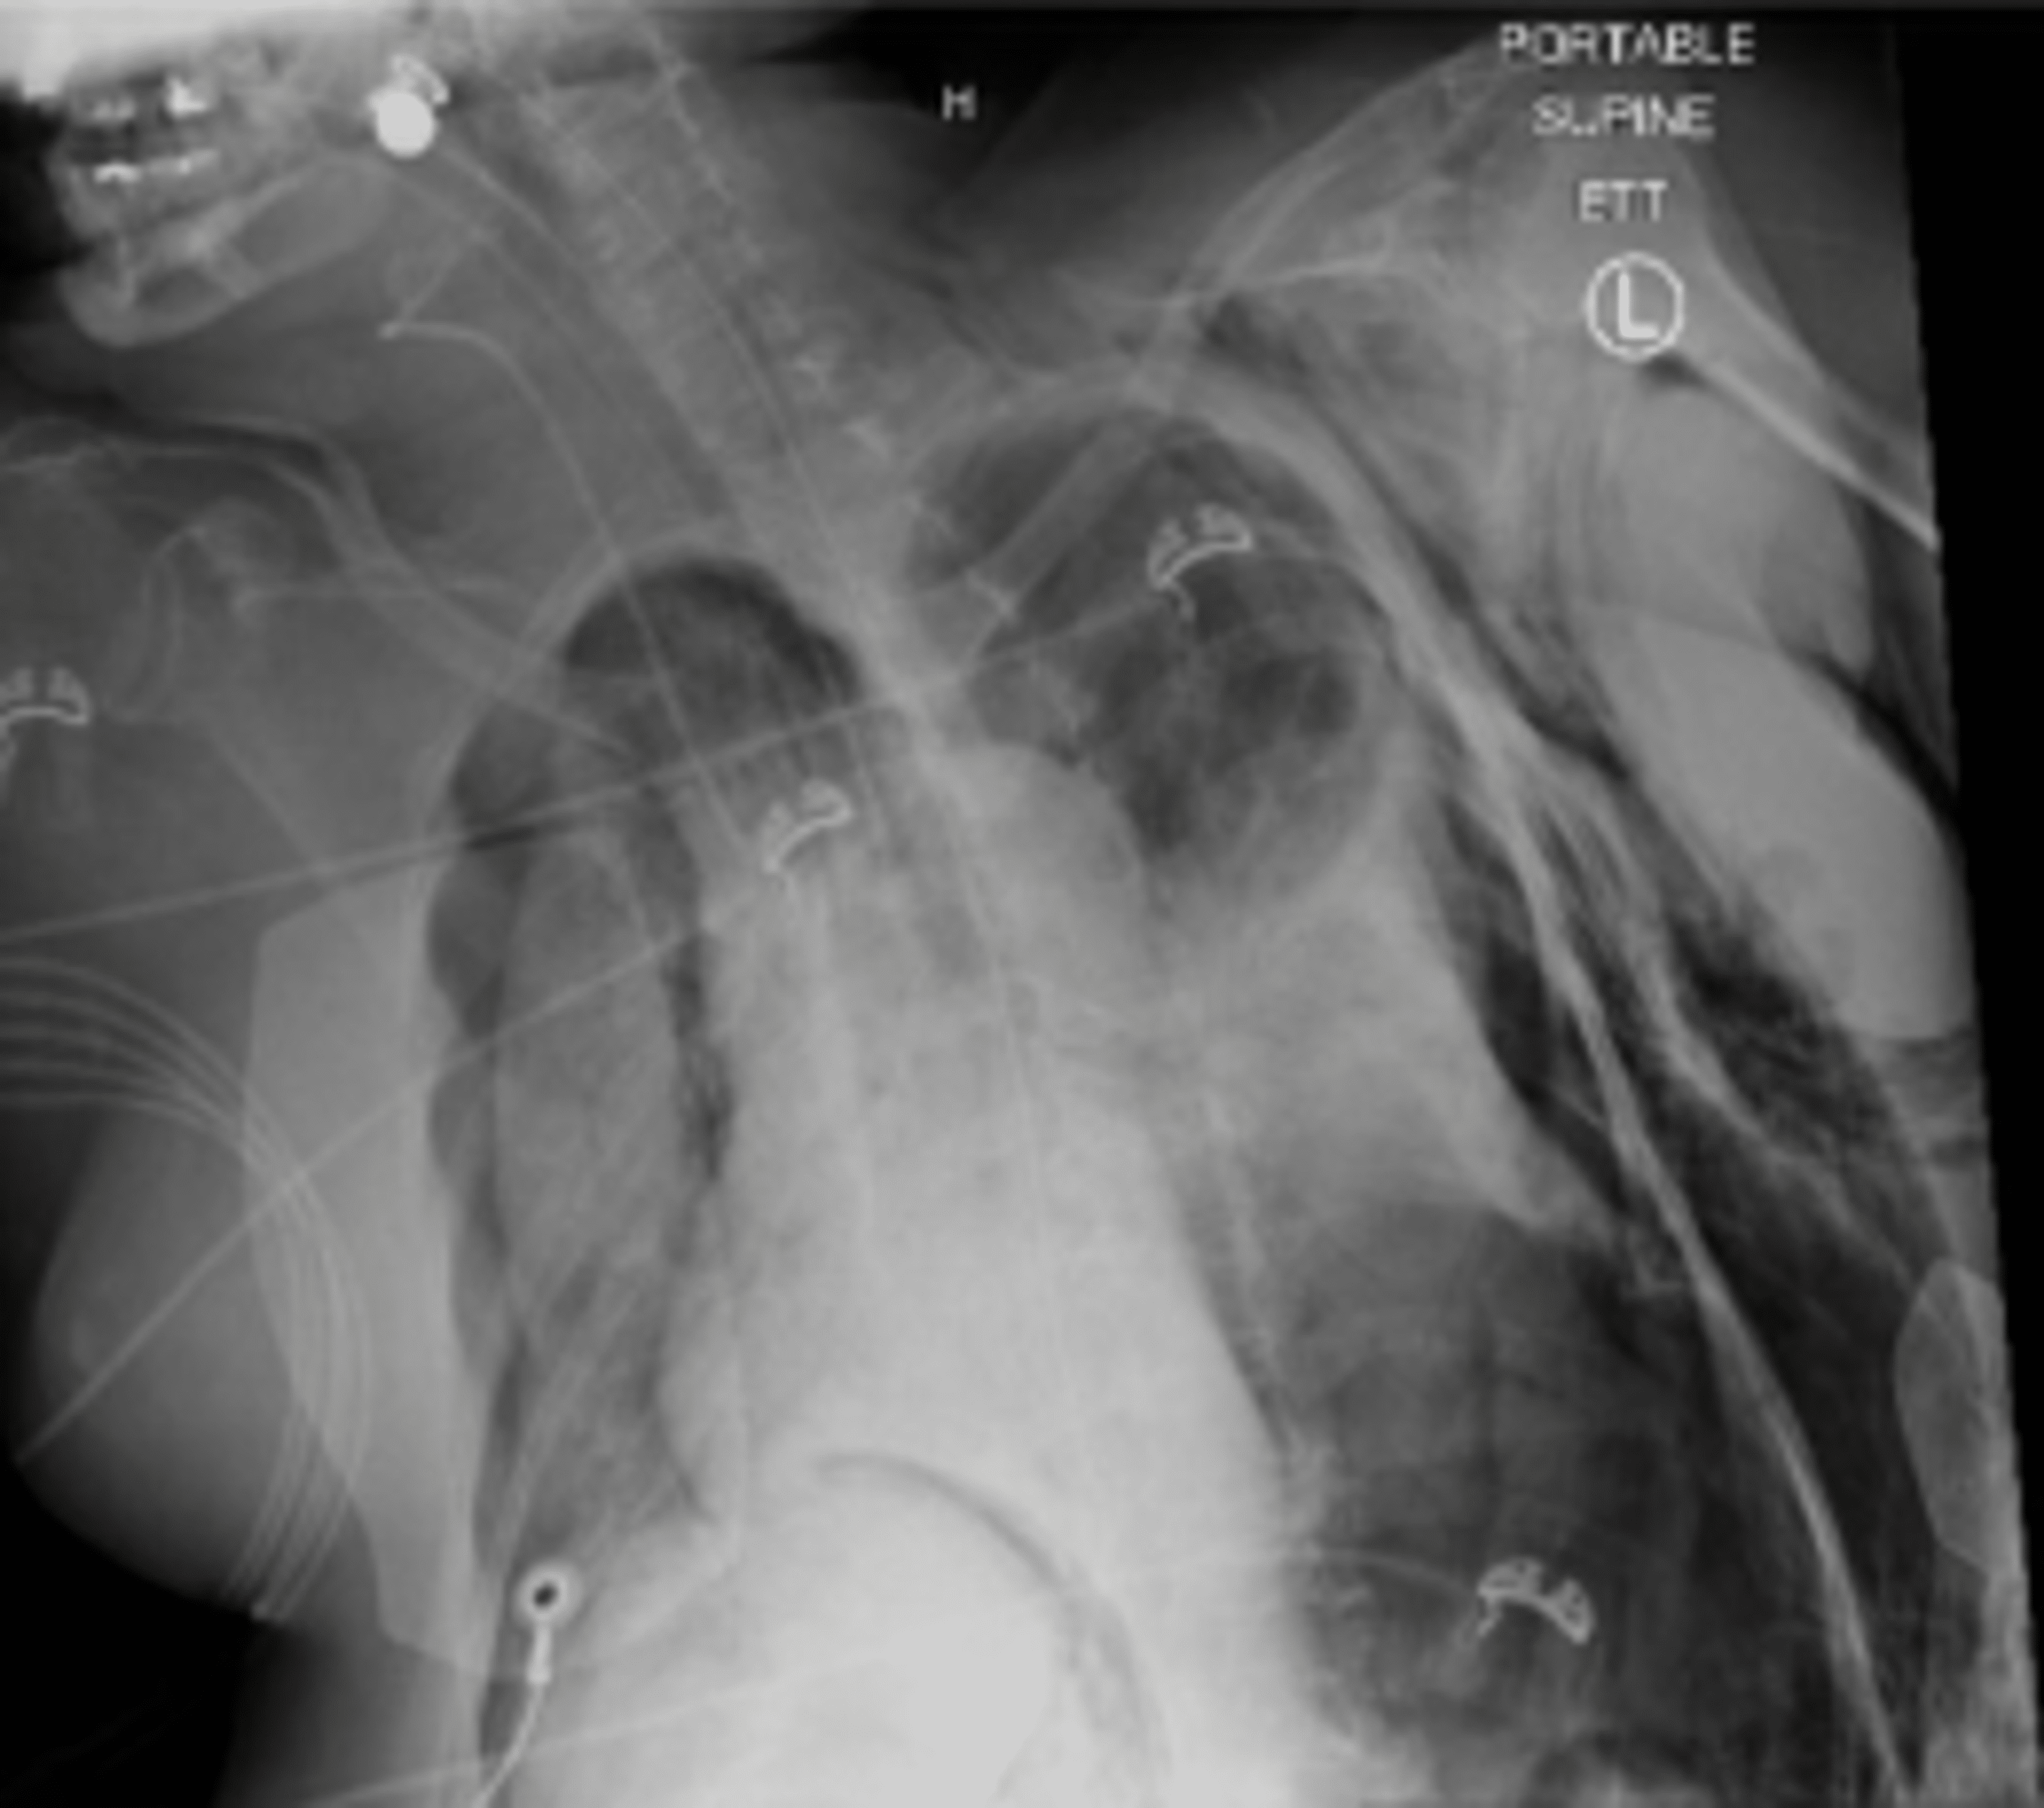

Barotrauma In Mechanical Ventilation . Web there is no single strategy to prevent pulmonary barotrauma on patients on mechanical ventilation. The most efficient mechanism that. Web pulmonary barotrauma was the most common complication of mechanical ventilation, but modern strategies have. Web pulmonary barotrauma can complicate mechanical ventilation. It is most often due to alveolar rupture resulting in. Web pulmonary barotrauma is a complication of mechanical ventilation and has correlations with increased morbidity.

Web pulmonary barotrauma is a complication of mechanical ventilation and has correlations with increased morbidity. The most efficient mechanism that. Web pulmonary barotrauma was the most common complication of mechanical ventilation, but modern strategies have. Web there is no single strategy to prevent pulmonary barotrauma on patients on mechanical ventilation. Web pulmonary barotrauma can complicate mechanical ventilation. It is most often due to alveolar rupture resulting in.